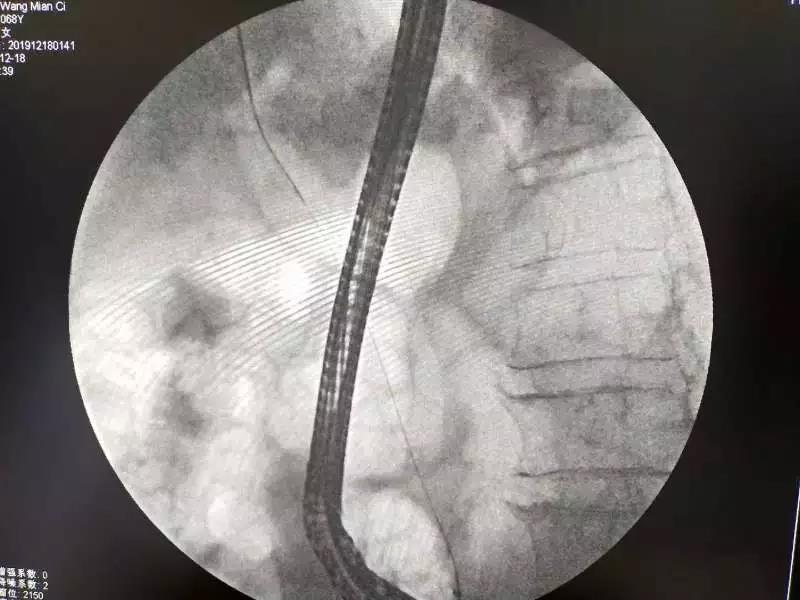

经内镜逆行胰胆管造影(ERCP)是目前公认的诊断和治疗胆胰管疾病的金标准,在此基础上进行鼻胆汁引流术(ENBD)、胆管支架植入术、胰管支架植入术等,具有不开刀、创伤小、安全性高、并发症少、住院时间短、恢复快等优点,尤其是对于年龄较大、伴发病和并发症较多、外科手术风险较大的患者,因ERCP疗效确切和微创的特点,目前已成为胆胰疾病的首选诊疗方法之一。

(术后影像资料 )